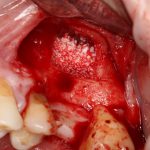

Простой синуслифтинг. Часть I.